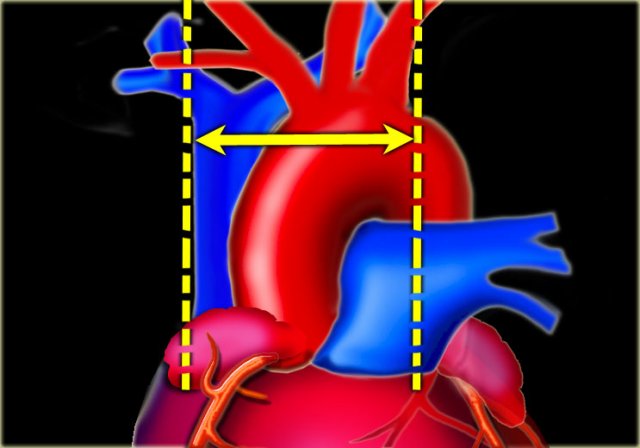

The cardiothoracic ratio (CTR) is the ratio of the transverse diameter of the heart to the internal diameter of the chest at its widest point just above the dome of the diaphragm as measured on a PA chest film.

An increased cardiac silhouette is almost always the result of cardiomegaly, but occasionally it is due to pericardial effusion or even fat deposition.

The heart size is considered too large when the CTR is > 50% on a PA chest x-ray.

The vascular pedicle is bordered on the right by the superior vena cava and on the left by the left subclavian artery origin (6).

The vascular pedicle is an indicator of the intravascular volume.

A vascular pedicle width less than 60 mm on a PA chest radiograph is seen in 90% of normal chest x-rays.

A vascular pedicle width of more than 85 mm is pathologic in 80% of cases.

5 mm increase in diameter corresponds to 1 liter increase of intravascular fluid.